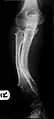

Multiple osteochondromas causing deformity of the forearm (shortening of the Radius with secondary bowing of the Ulna).